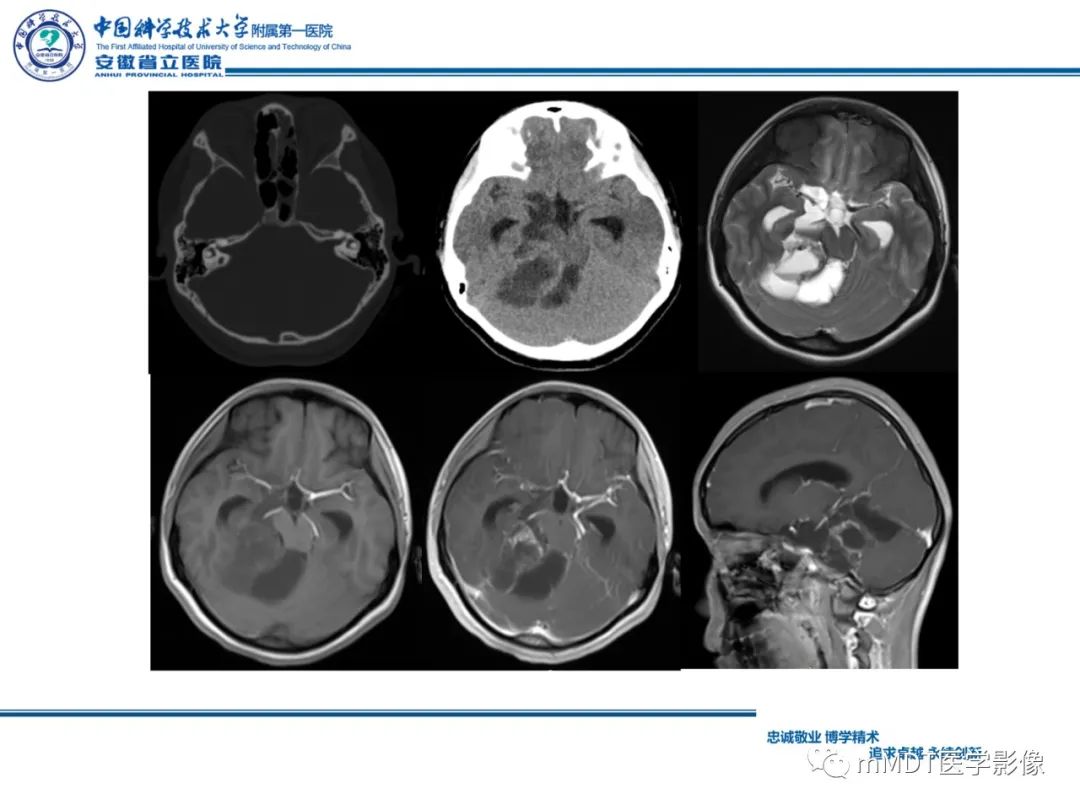

【PPT】毛细胞型星形细胞瘤病例解析